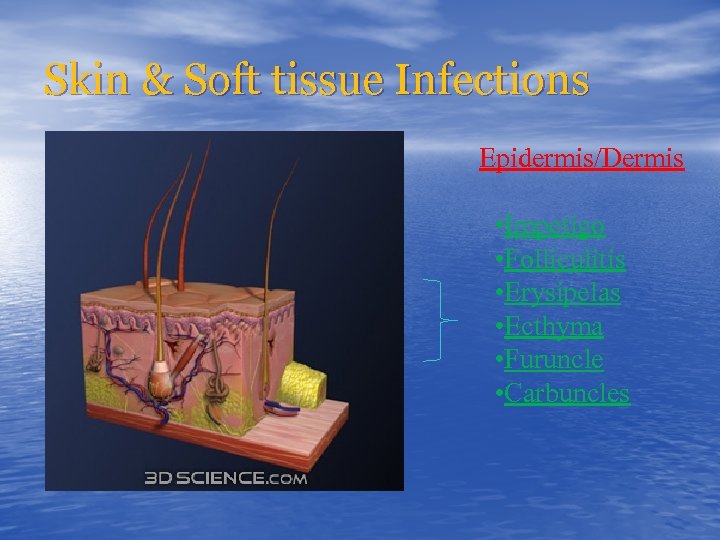

Skin & Soft tissue Infections Epidermis/Dermis • Impetigo • Folliculitis • Erysipelas • Ecthyma • Furuncle • Carbuncles

Skin & Soft tissue Infections Epidermis/Dermis • Impetigo • Folliculitis • Erysipelas • Ecthyma • Furuncle • Carbuncles